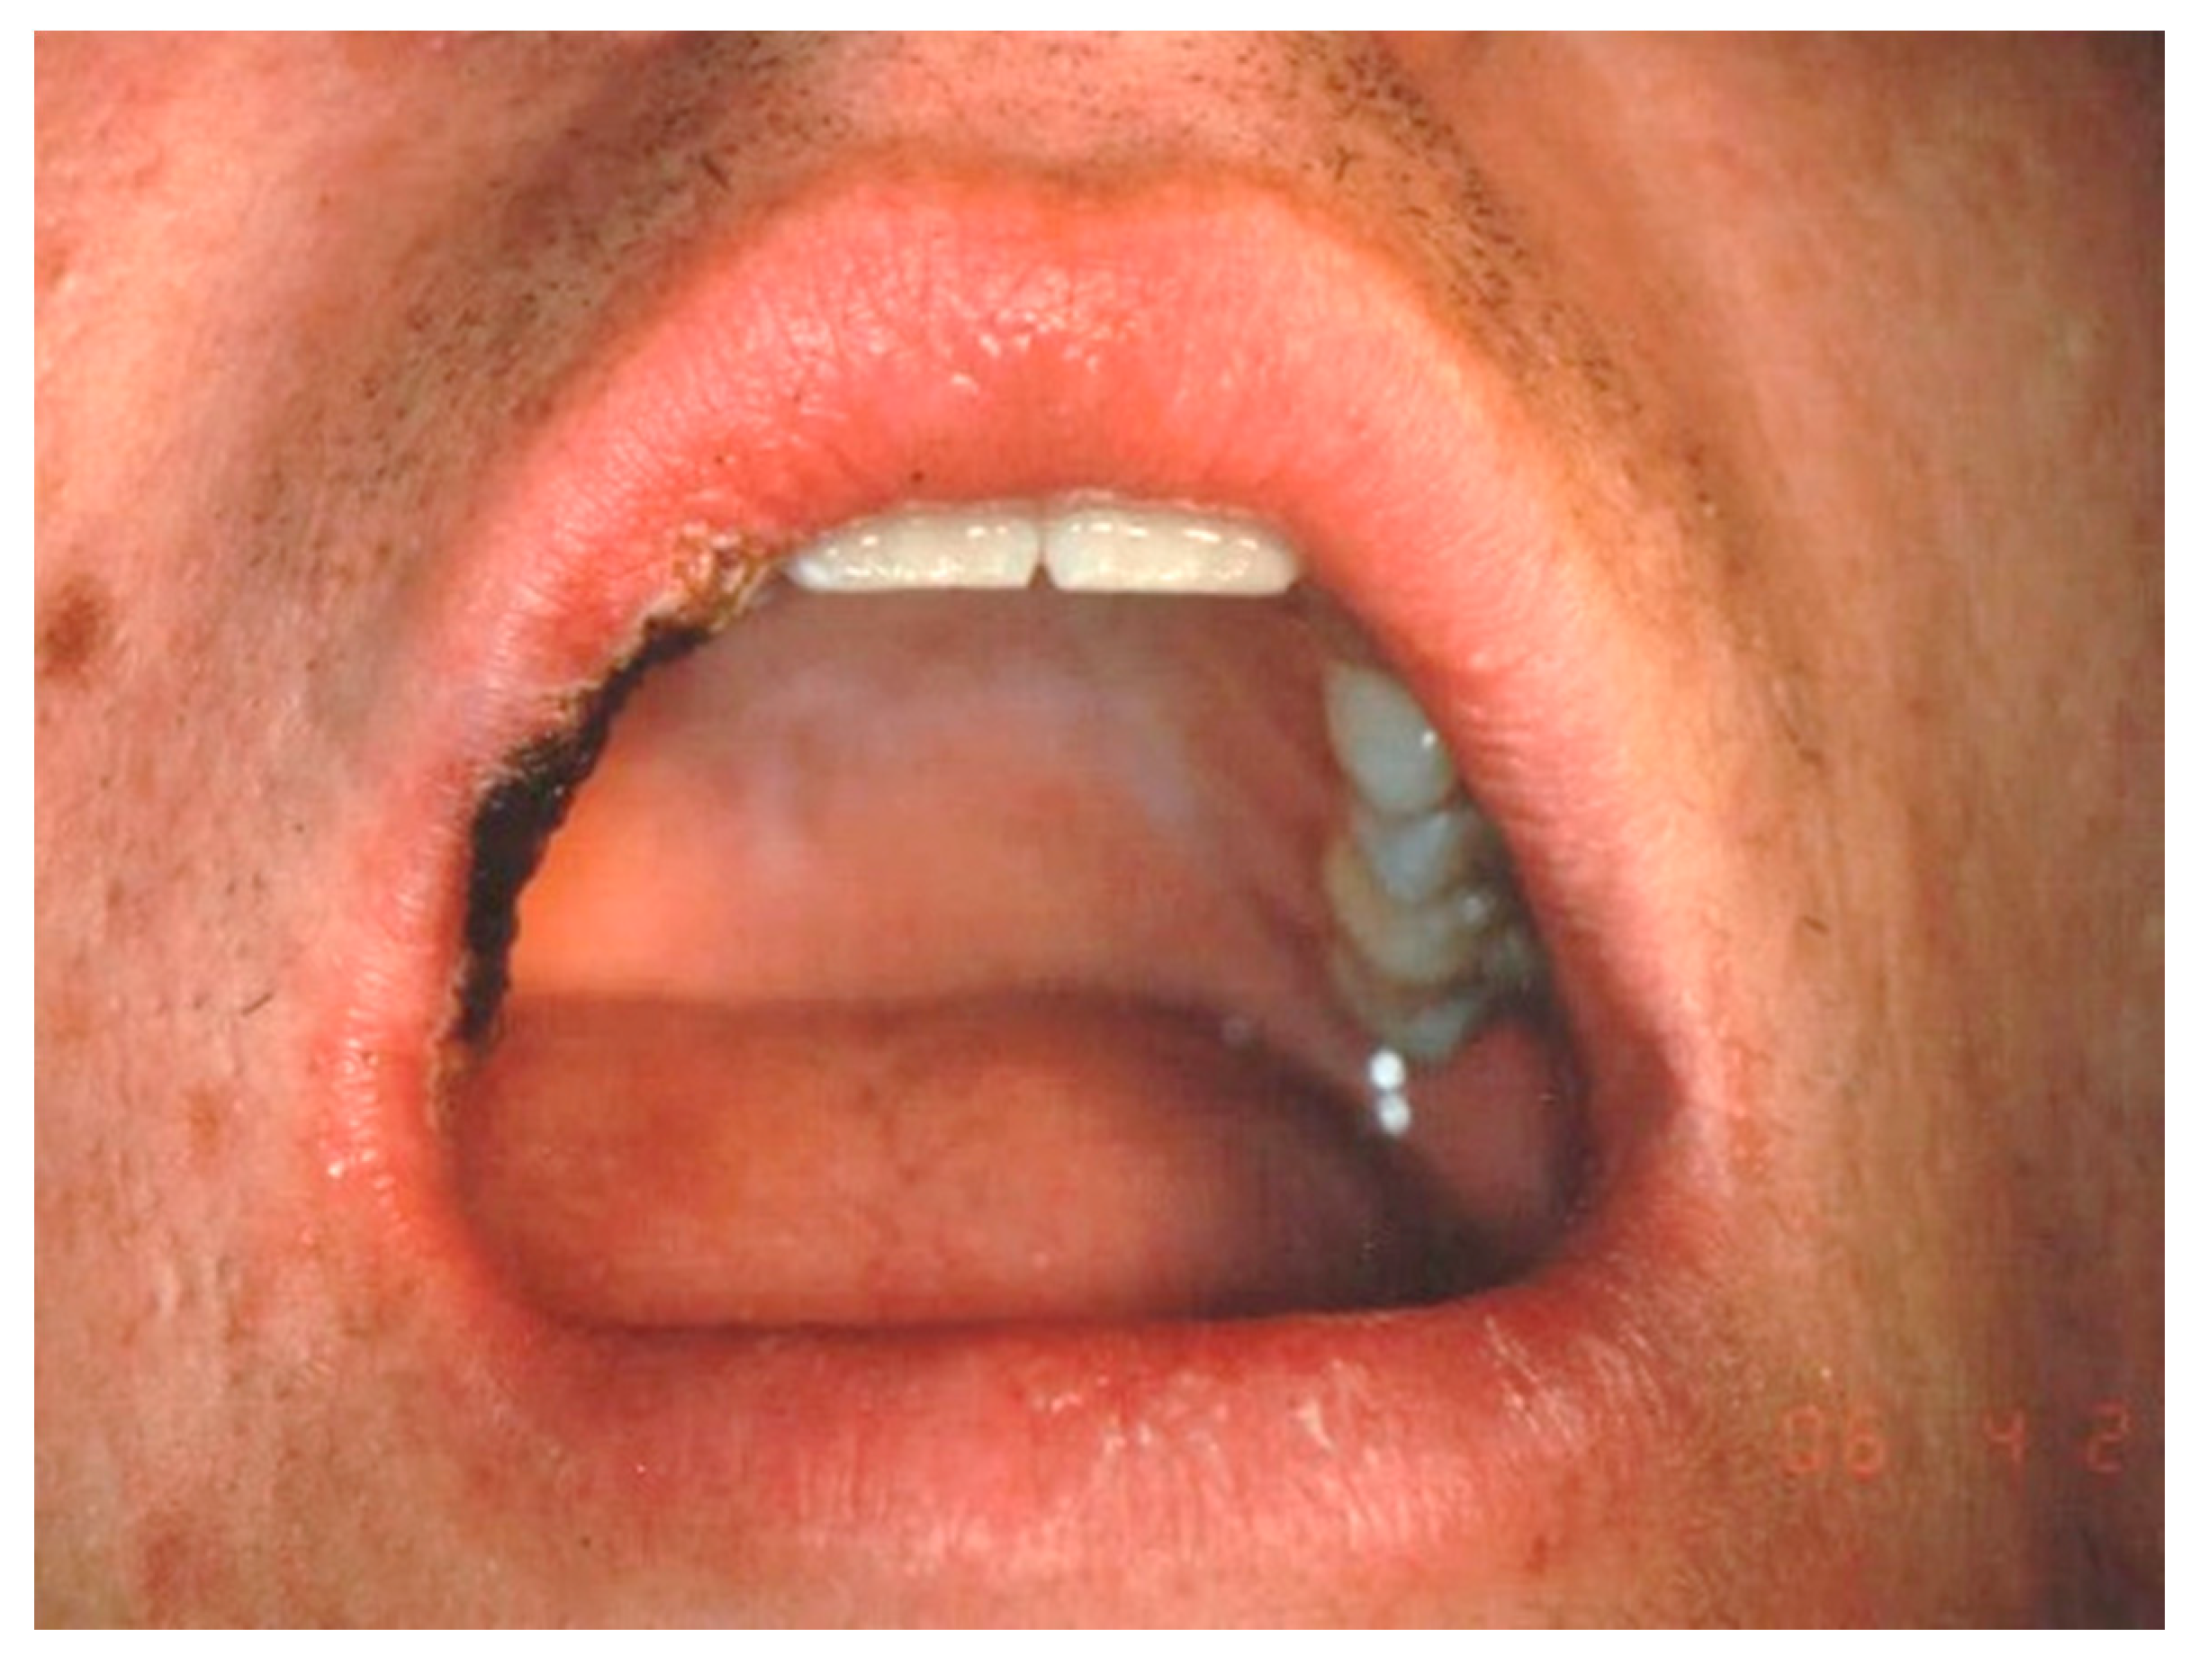

Figure 7.

Clinical aspect of the lesion VM on the lower lip.

Figure 8.

The lesion was treated by transmucosal photo-thermo-coagulation after topical anesthesia application. An Nd:YAG laser was used.

2.3.3. Nd:YAG Laser Irradiation

An Nd:YAG laser with a wavelength of 1064 nm (Fidelus plus, Fotona medical laser, Ljubljana, Slovenia) was used. After topical application of local anesthesia, a transmucosal photo-thermo-coagulation was made in noncontact mode, with an output power of 2 Watts, fiber diameter of 320 μm, pulsed mode (15 Hz), pulse duration of 320 µs (LP mode), and an energy density of 11.94 J/cm2. The lesion was treated by transmucosal photo-thermo-coagulation, and the treatment was considered completed when a blanching and visible shrinkage of the blood appeared inside the CV or VM (Figure 7 and Figure 8). When necessary, a second passage of the photo-vaporization cycle was performed after 2 weeks in cases of persistence or recurrence of the lesion. The wound was left to heal without any other treatment, and no sutures were made.